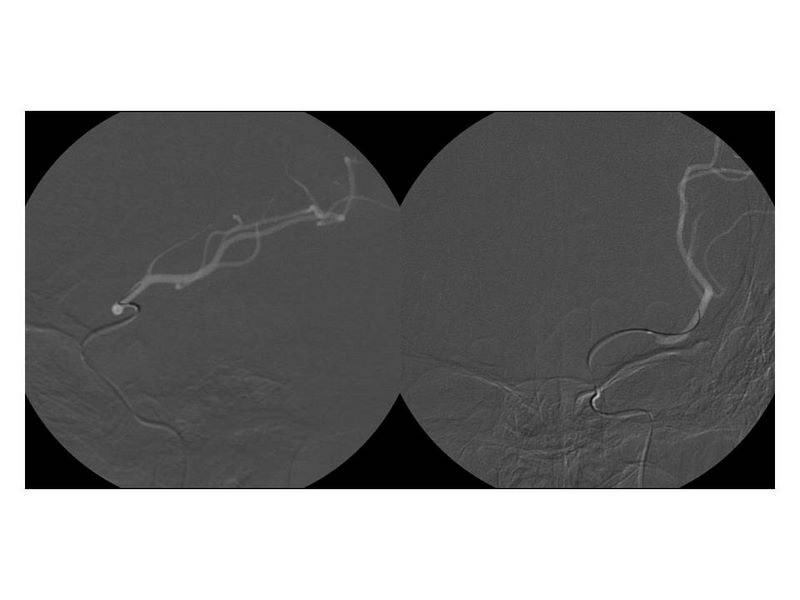

Ictus con stent